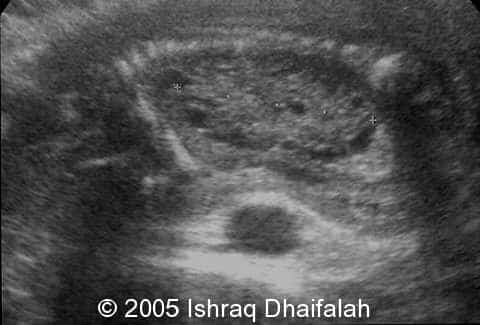

Transverse and longitudinal sections demonstrating the hyperechoic and polycystic kidneys in fetus B:

image4